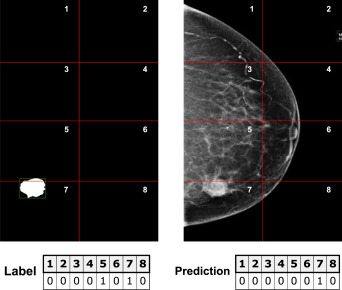

图5.补丁监督方法的简化示例:左侧显示的是图像掩码,分割成补丁并转换为下面的标签向量,其中每个值对应一个补丁:索引5和7设为1,因为它们各自的补丁包含病灶。右侧显示的是按照相同结构对每个图像补丁进行的假设预测:在此示例中,除了补丁5之外,所有补丁都正确预测。